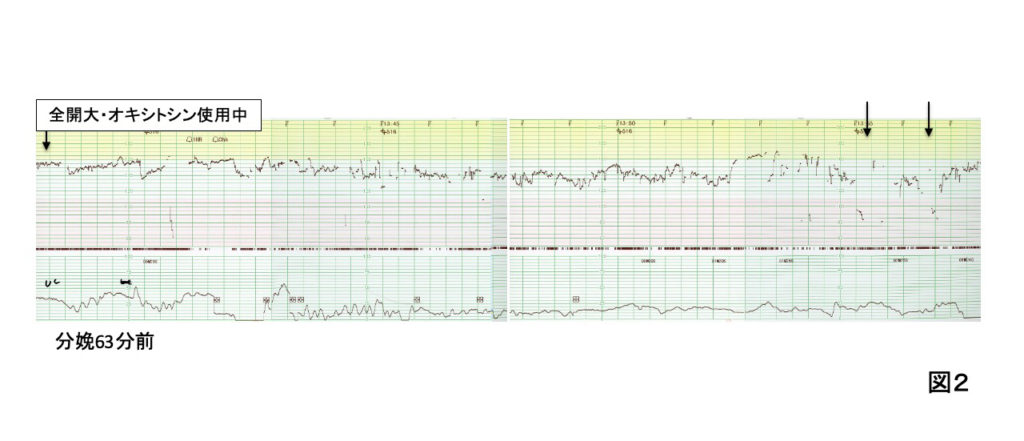

2.分娩63分前(全開大)から43分前までのCTG判読と経過(図2)

心拍数基線は140bpmで、細変動は10-15bpmと正常範囲にあり、最後のあたりから軽度一過性徐脈(↓)が出現している。早発一過性と判読しても、変動一過性と判読してもレベル2にあたる。

患者背景にリスクはなく、妊娠経過に異常はない。破水後12時間で、陣痛発来し、バイタルサインや血液検査に感染の兆候はない。

現場は、体位変換で経過を観察した。